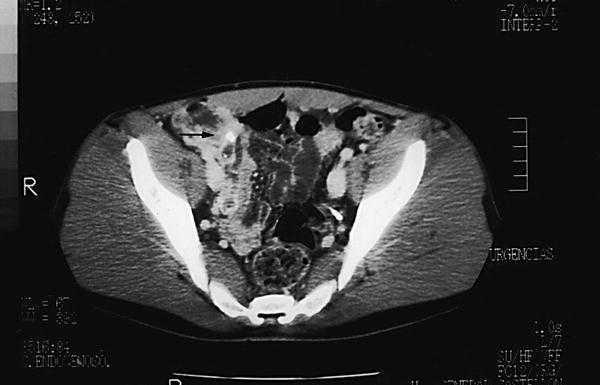

Se solicitó de urgencias, una radiografía simple de abdomen (fig. 1) en la que se observó una imagen densidad calcio, en capas concéntricas, proyectada sobre fosa ilíaca derecha, compatible con apendicolito, tras la cual se decidió solicitar una ecografía abdominal y de fosa ilíaca derecha (fig. 2), en la que se evidenció la existencia de un asa fija, aperistáltica, con su base en el ciego, que terminaba en dedo de guante, dolorosa a la presión y que media más de 6 mm, con una distribución en capas de ecogenicidad alternante y con imagen cálcica en su extremo distal, hallazgo que posteriormente se confirmó con la tomografía computarizada (TC) abdominopélvico (fig. 3). Por todo ello se realizó el diagnóstico de apendicitis aguda catarral-flemonosa, con apendicolito distal.

Fig. 2.